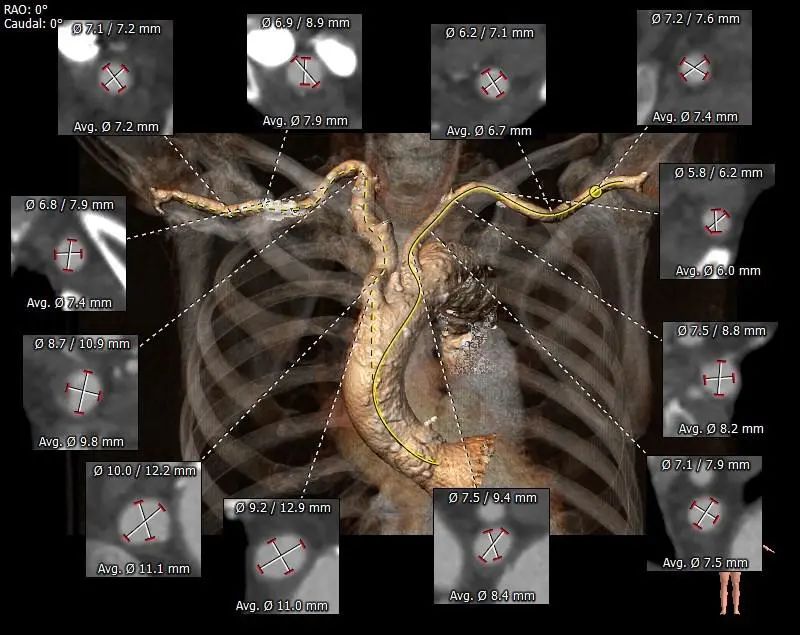

主动脉根部评估

根部概览

• 该患者外周多发附壁血栓,合并胸主、腹主及髂总动脉瘤,动脉瘤巨大,并且内由附壁血栓,经股动脉行TAVR手术血管并发症风险极高。测量发现双侧锁骨下动脉内径可,预计采用左锁骨下动脉为主入路,右股动脉为辅入路。